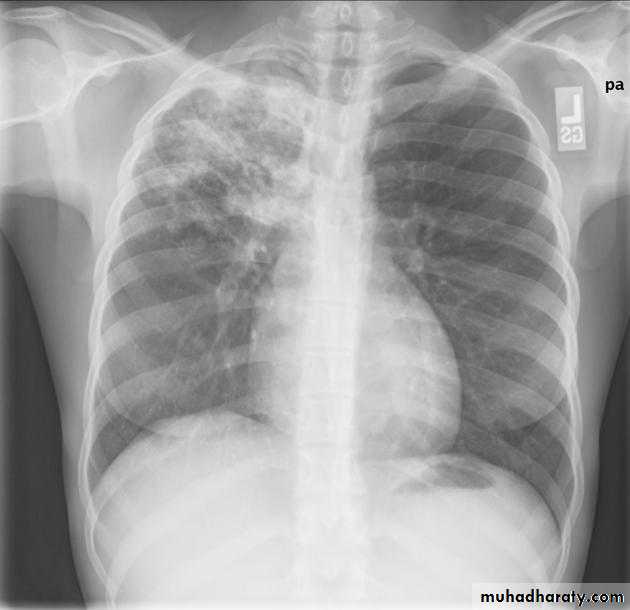

Miliary TB

65.Miliary TB

66.miliary TB